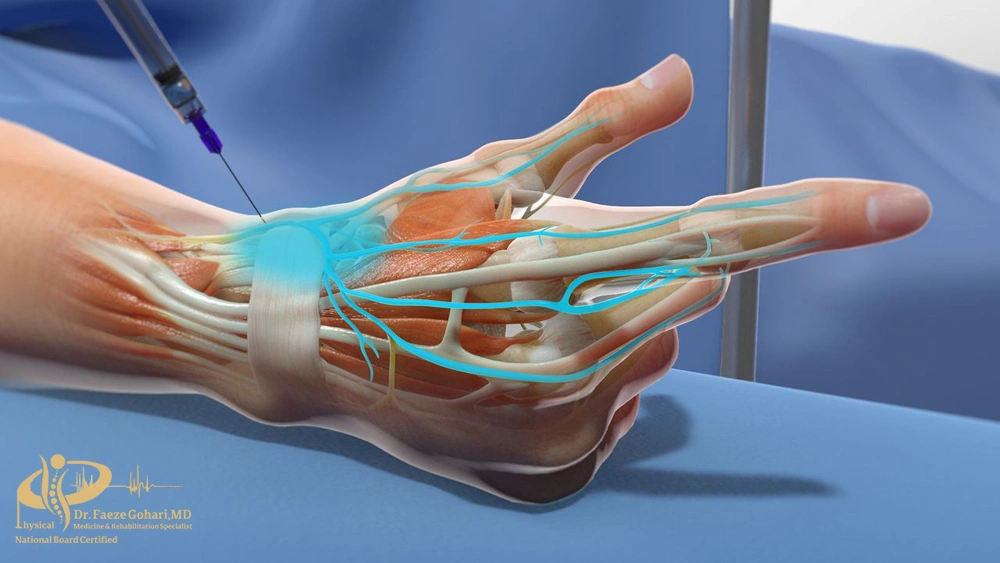

| سندرم تونل کارپال (فشردگی عصب مدیان) |

| اثر و ماندگاری |

| بلوک عصبی میتواند التهاب اطراف عصب مدیان را کاهش دهد و علائمی مانند درد، گزگز و بیحسی انگشتان را تسکین بخشد. این روش معمولاً در بیمارانی استفاده میشود که درمانهای محافظهکارانه نتیجه نداده و هنوز کاندید جراحی نیستند؛

ماندگاری معمولاً ۲ تا ۴ هفته |

نحوه انجام بلوک عصبی اندامهای فوقانی

فیلم بلوک عصبی مچ دست

بلوک عصبی در اندامهای فوقانی بهصورت سرپایی و کمتهاجمی انجام میشود. پزشک بسته به محل درد و هدف درمان (تشخیصی یا درمانی)، عصب یا شبکه عصبی مناسب را انتخاب کرده و با هدایت تصویری سونوگرافی (و در برخی موارد فلوروسکوپی) سوزن ظریف را در مجاورت عصب قرار میدهد. سپس بیحسی موضعی بهتنهایی یا همراه با کورتون بهصورت تدریجی تزریق میشود تا انتقال پیامهای درد مهار و التهاب کاهش یابد. بیمار پس از پایش کوتاهمدت همان روز مرخص میشود.

- تعیین مسیر تزریق با هدایت تصویری: مسیر ایمن ورود سوزن با سونوگرافی یا در موارد خاص با فلوروسکوپی مشخص میگردد تا عصب و عروق بهدقت شناسایی شوند.

- بیحسی پوستی و ورود سوزن: ابتدا پوست با داروی موضعی بیحس میشود و سپس سوزن باریک تحت هدایت تصویربرداری وارد بافت میگردد.

- اقدامات ایمنی پیش از تزریق: با انجام آسپیراسیون منفی یا استفاده از ماده حاجب/داروی محرک، از ورود ناخواسته سوزن به عروق یا موقعیت نادرست آن جلوگیری میشود.

- تزریق مرحلهای دارو: داروی بیحسی با یا بدون کورتون بهصورت تدریجی تزریق میشود و پخش حلقهای آن اطراف عصب بررسی و در صورت نیاز موقعیت اصلاح میگردد.